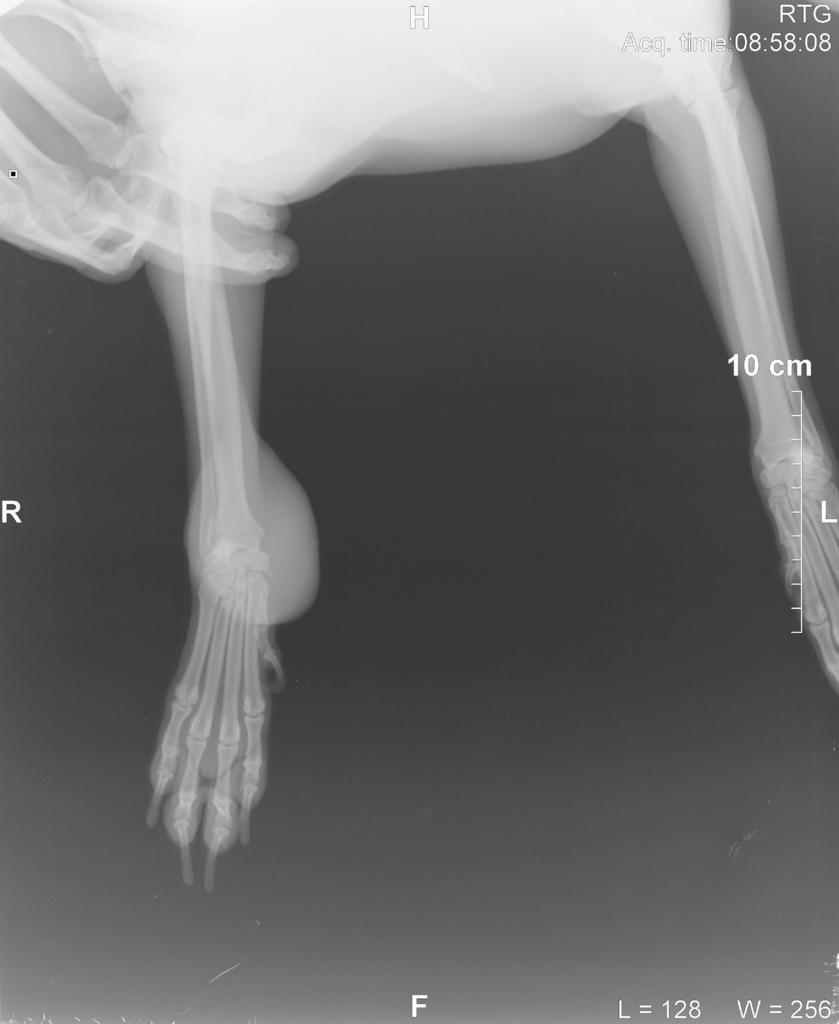

Dodalem w pierwszym poscie rtg z dzisiaj i rtg z 05.02.2014 (5miesiecy wczesniej to zdjecie w srodku)

[COLOR=#000000][FONT=Verdana]Witam, moja 10 letnia sunia ma taka wielka narosl na lapie.. ani to ja nie boli nie kuleje ani nic.. jest to miekkie, na poczatku jak bylo male byl robiony rentgen ale nie bylo zadnych zmian patologicznych.. macie moze pomysl co to moze byc? w zalaczniku dalem zdjecie lapy. kostniakomiesak a moze tluszczak? nie wiem co tym sadzic.. w zalaczniku dalem zdjecie lapy psa.. prosze o rady i pomoc ;)[/FONT][/COLOR][attachment=3445:11639.attach]

U psiaka wszystko dobrze. guz w wielkosci pomaranczy..